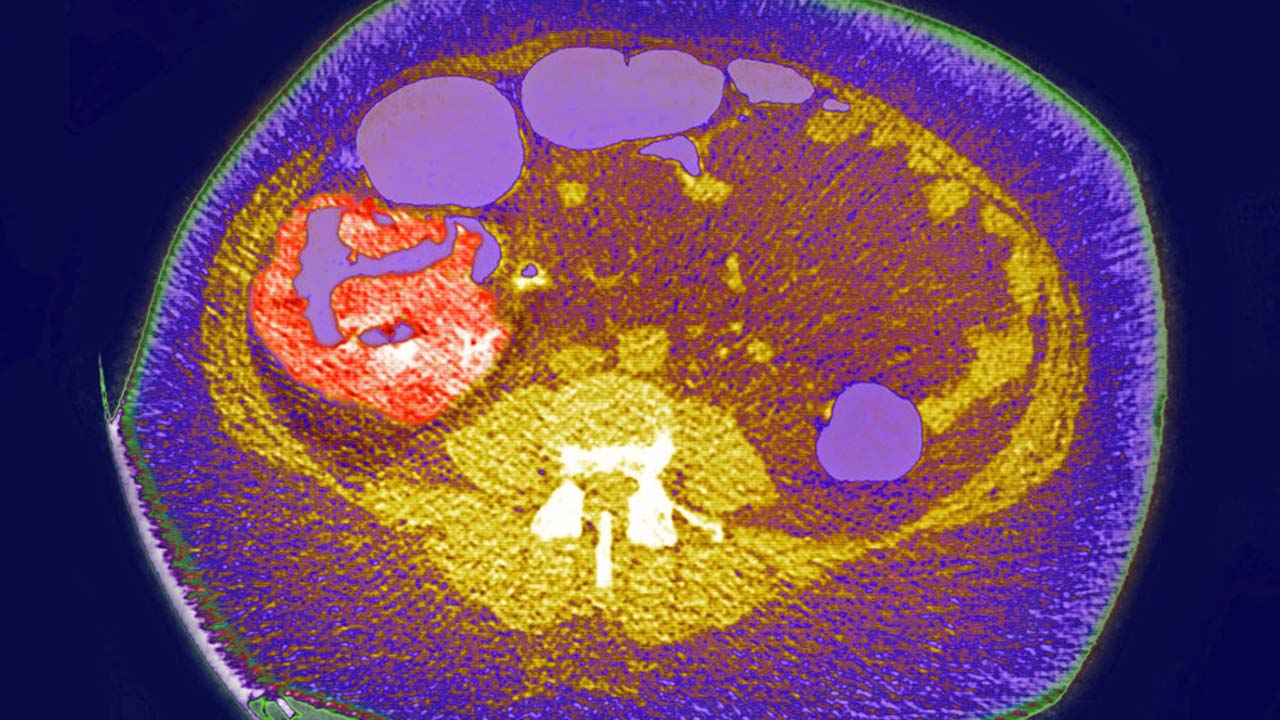

84cdf3d7-Colon cancer screening

FILE - Colon cancer, tumor on the caecum and ileocolic valve, visualization on a radial CT scan.